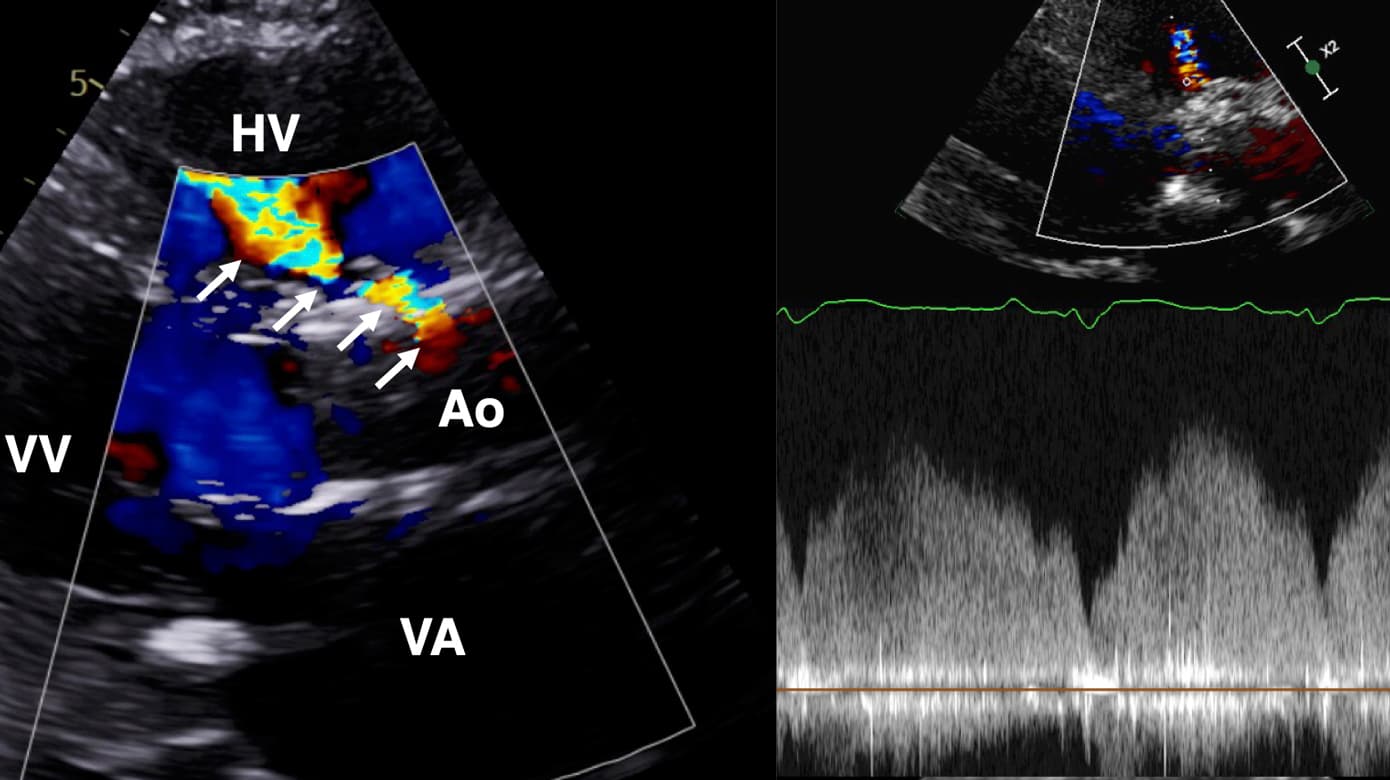

Akut ekkokardiografi påviste fistel fra aortaroden til højre ventrikel og hæmodynamisk betydende shunt (Figur 1 og video). Der var ikke ekkokardiografiske fund tydende på akut lungeemboli. Ved gennemgang af ekkokardiografier i forløbet seks uger tidligere var fistlen allerede til stede et døgn postproceduralt, men mindre udtalt. Trods understøttende behandling descenderede tilstanden hurtigt, og patienten afgik ved døden et døgn efter debut af de akutte smerter.

Akut forværring med svær rygsmerte, forhøjet D-dimerniveau, tiltagende shunt og udvikling af shock kan have været forårsaget af yderligere, akut fistulering og/eller dissektion i aorta ascendens. Blodtrykket var ikke forhøjet i døgnet op til de akutte smerter, og der var ingen oplagt forklaring på, hvorfor den akutte progression først indtraf seks uger postproceduralt. Umiddelbart efter de akutte smerter steg pulstrykket markant, foreneligt med den påviste diastoliske shunt fra aorta til højre ventrikel.